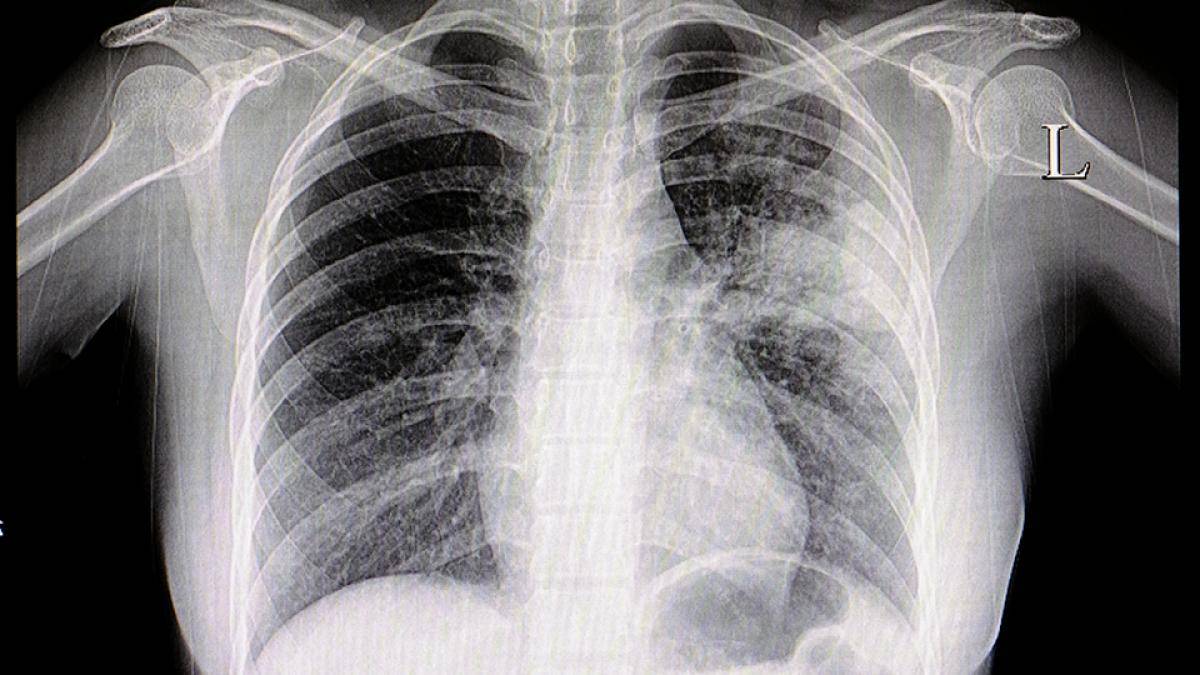

PneumoCAP était un projet de recherche national, mené par les départements de médecine générale des universités Paris Descartes et Paris Diderot, qui visait à identifier les caractéristiques (cliniques, biologiques et radiologiques) des pneumonie aigüe communautaire (PAC) à pneumocoque parmi l’ensemble des PAC à radiographie pulmonaire positive prises en charge en médecine générale.

Cette étude était menée dans un contexte de surprescription d’antibiotiques, à la suite d'une étude observationnelle ambulatoire (appelée "CAPA") qui avait montré que, quelle que soit la clinique et les résultats de la radiographie pulmonaire, tous les patients ayant une suspicion de PAC recevaient systématiquement des antibiotiques. Cette étude visait donc à distinguer les PAC qui nécessitaient une antibiothérapie précoce (PAC à pneumocoque à risque d’infection invasive) de celles pour lesquelles une autre stratégie était envisageable.